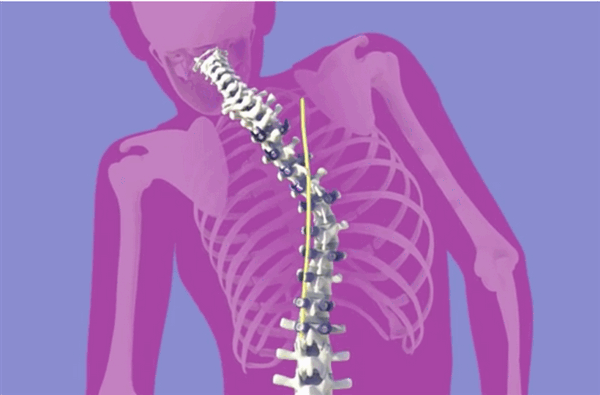

Эти операции основаны на установлении специальных спинальных конструкций, которые выполняют роль «домкрата», вытягивая позвоночник и исправляя искривление.

Пациенту в дужки позвонков вкручивают винты, на которые затем устанавливается металлическая пластина. Эта пластина и является каркасом для позвоночника. Позвонки тянутся за винтами и происходит выпрямление позвоночного столба. Пластина находится в подкожном слое и не мешает нормальной жизни. После выравнивания ее удаляют.

Лечение сколиоза 3 степени у детей до 10 лет проводится с применением подвижных фиксаторов, что позволяет позвоночнику беспрепятственно расти и формироваться. Детям старше 13 лет и взрослым больше подходят неподвижные фиксирующие конструкции. Но в обоих случаях они устанавливаются единожды и не предполагают удаления в дальнейшем. Снятие корригирующего устройства проводится крайне редко. Оно возможно в единичных случаях исключительно при возникновении непредвиденных осложнений.